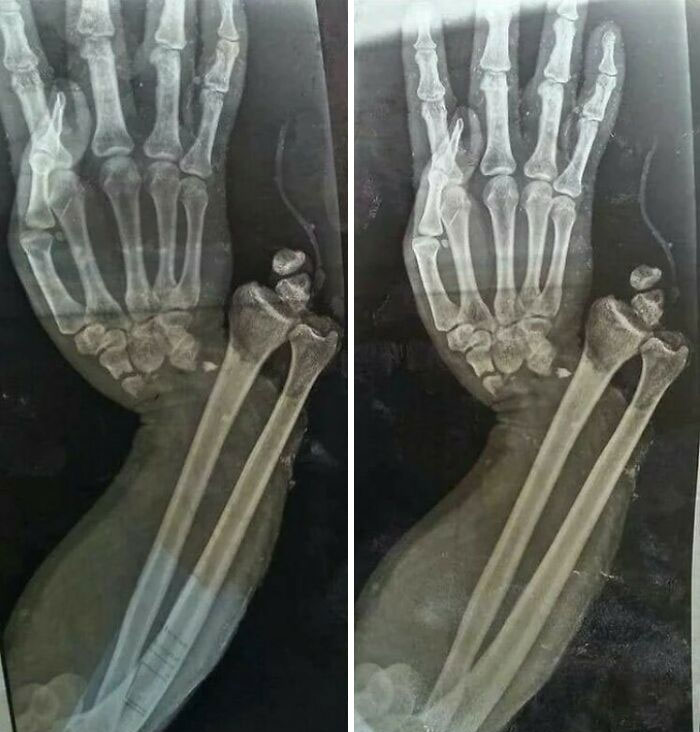

Open fracture dislocation of the wrist